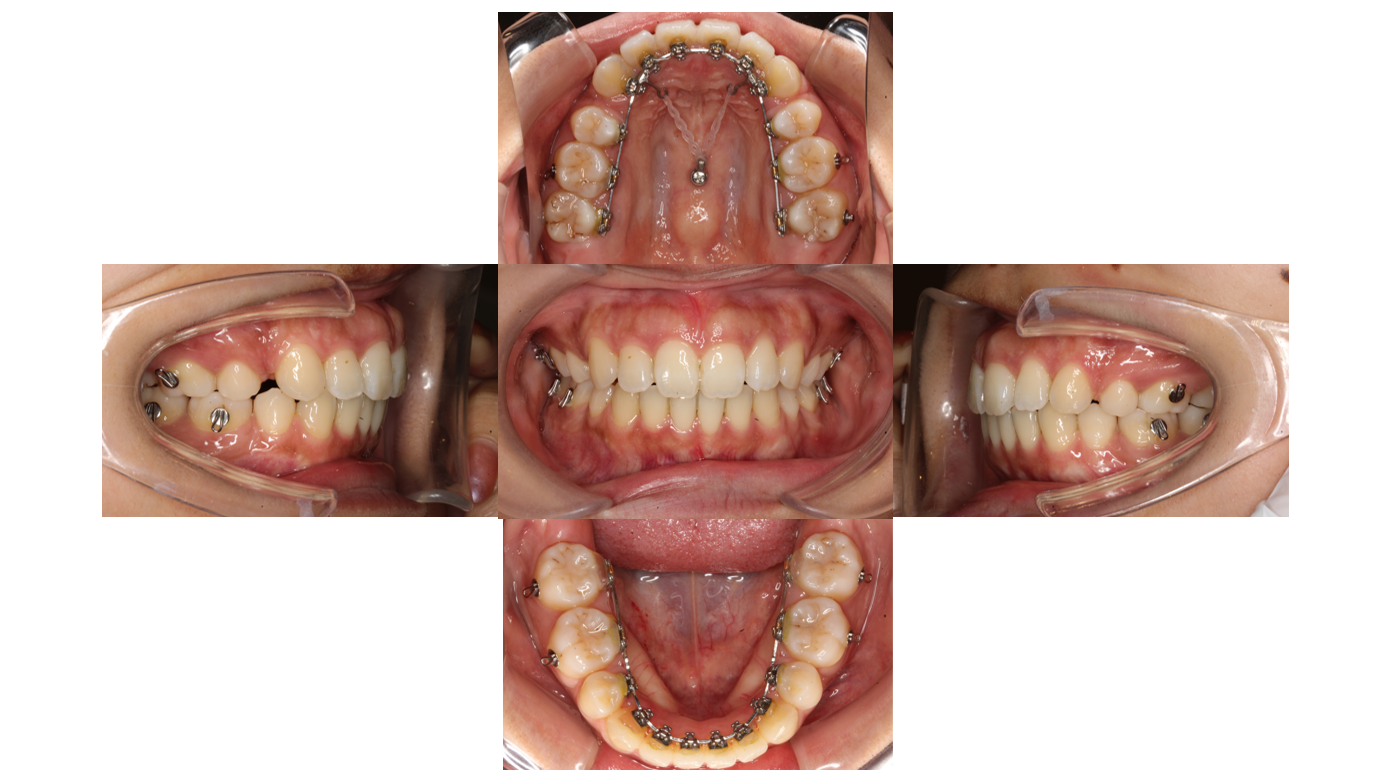

初診

装置装着後

装置が裏側につきました

青い材料は歯と装置が当たらないように付与しています